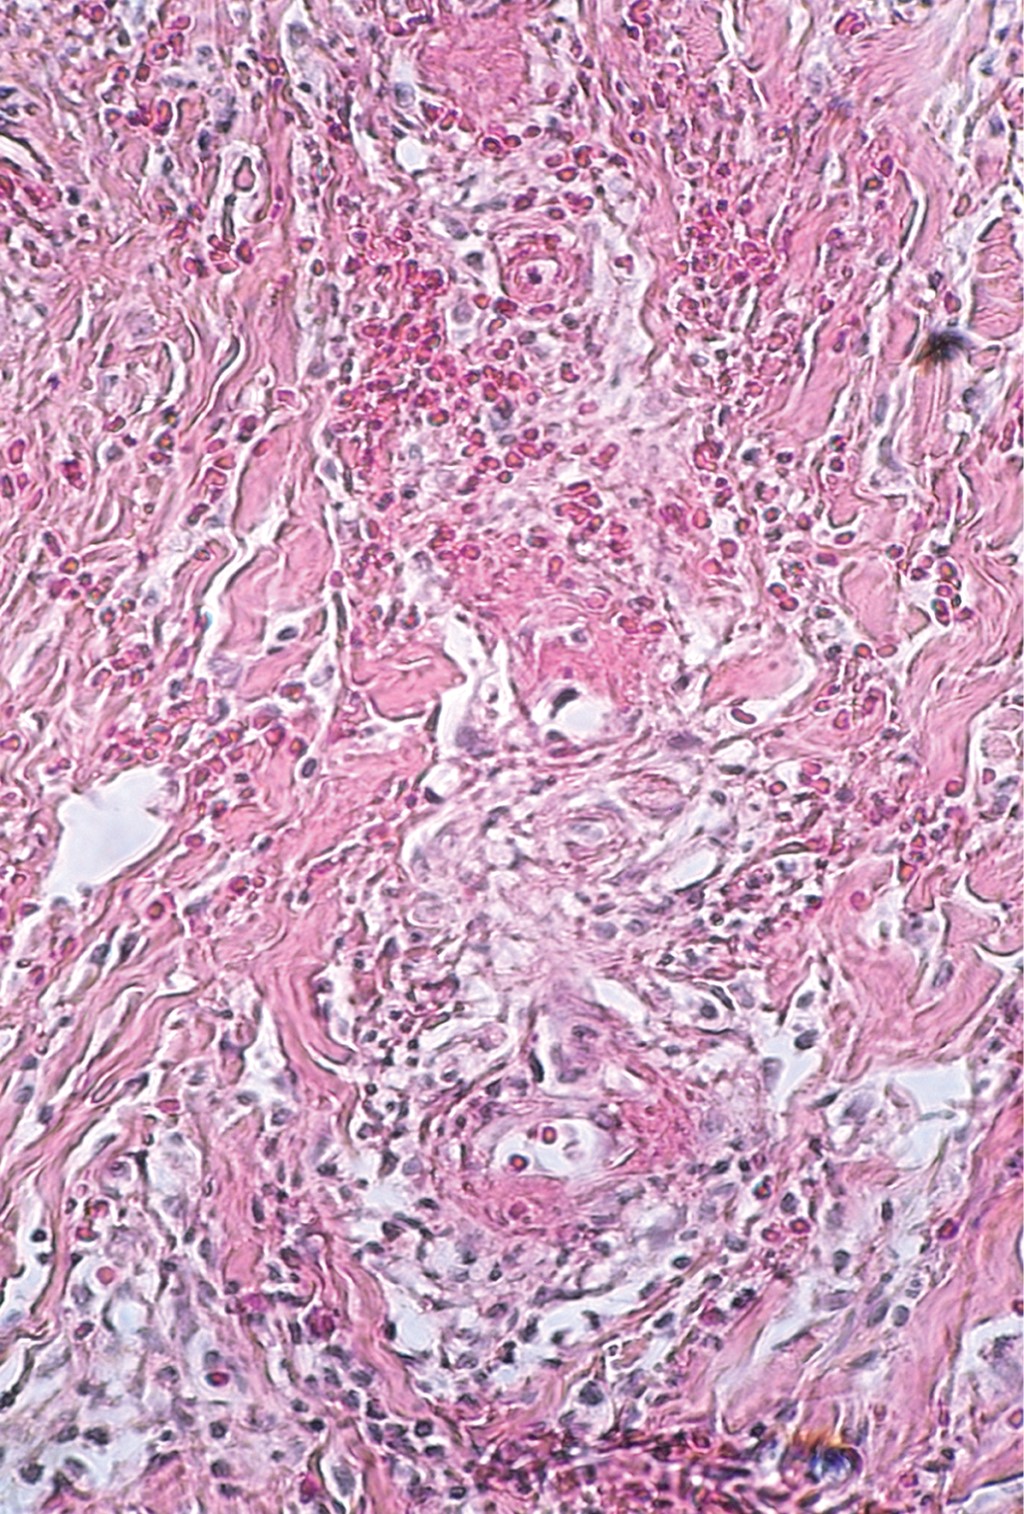

Cutaneous polyarteritis nodosa: presentation of two cases and literature review

Cutaneous polyarteritis nodosa is a form of vasculitis that affects small to medium sized arteries, with unknown incidence due to a low frequency. The exact etiopathogenesis is unknown. Clinically, it is characterized by painful subcutaneous nodules associated to livedo reticularis, that frequently evolves to ulcers on lower extremities, with a chronic and relapsing clinical course. Generally, it only involves skin, however, extracutaneous manifestation has been reported. In this article we describe different clinical presentation and management of two patients with different gender and age.

Figure 4